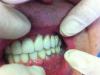

Wasja Опубликовано 9 июля, 2013 Поделиться Опубликовано 9 июля, 2013 Доброго времени суток, доктора! Пришел на контрольный осмотр пациент с работой 2009 г.в. Тогда как раз переходил с radix на adin, поэтому во рту получился такой микс. Вопросы почему и чем помочь. Работа тотальная и хотелось бы обойтись минимумом крови. Ссылка на комментарий

Zborzh Опубликовано 9 июля, 2013 Поделиться Опубликовано 9 июля, 2013 (изменено) Лучше бы переделать... Винты низкого уровня,как и работа . В позициях клыков имплантаты установлены протетически некорректно (далеко вне зоны воображаемого эстетического окна,слишком вестибулярно). Я бы тут посоветовал балочную конструкцию. Интересно мнение Doc'а. Изменено 9 июля, 2013 пользователем Zborzh Ссылка на комментарий

Wasja Опубликовано 14 июля, 2013 Автор Поделиться Опубликовано 14 июля, 2013 вы дали очень мало информации: по хорошему здесь бы выложить кт челюстей и нормальные фото зубных рядов и так далее. как я себе вижу - планировать временное протезирование на имплантах которые ОСТАЮТСЯ - планировать операцию по удалению части имплантов + установка новых имплантов + пластика кости (если требуется) + пластика десны. может так получиться что и не поставить сразу туда куда хочется. соответственно сначала пластика кости. потом уже имплантация. - осуществить операцию - осуществить временное протезирование - разбираться дальше (десна)Костной ткани достаточно во всех позициях имплантатов.Думаю убрать периимплантитные опоры и сразу поставить временные подковы.Хотя так неохота идти на тотальную переделку)... Ссылка на комментарий